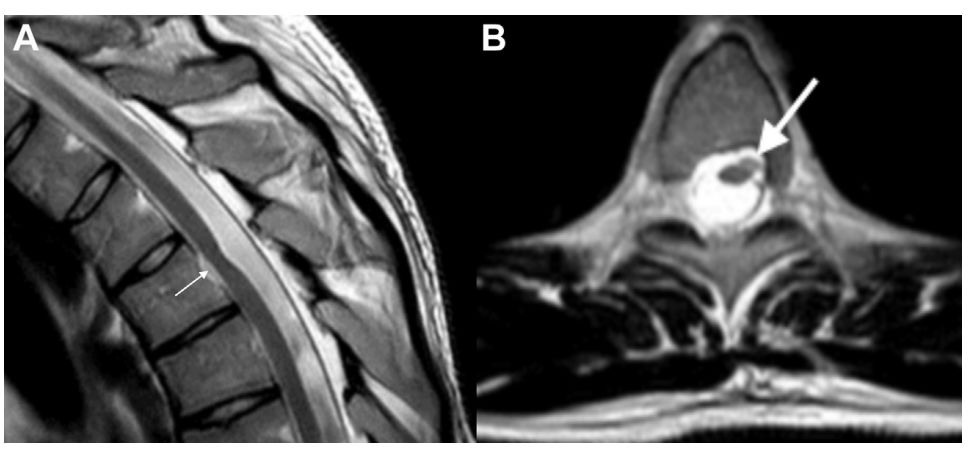

24岁男性患者,出现胸髓左侧半切综合征(图1),无外伤史。在严密的电生理监测下行手术治疗,术中切除部分疝出物,占位效应缓解(图2),术后无神经功能障碍。手术标本进行HE染色、免疫组化染色及甲基化检测。

图1. A.MRI-T2 矢状位可见T4节段疝出;B.轴位脊髓疝出偏向左侧。